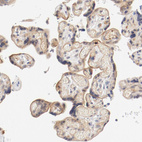

Immunohistochemical staining of human lymphoid tissues shows weak cytoplasmic positivity in germinal center cells.